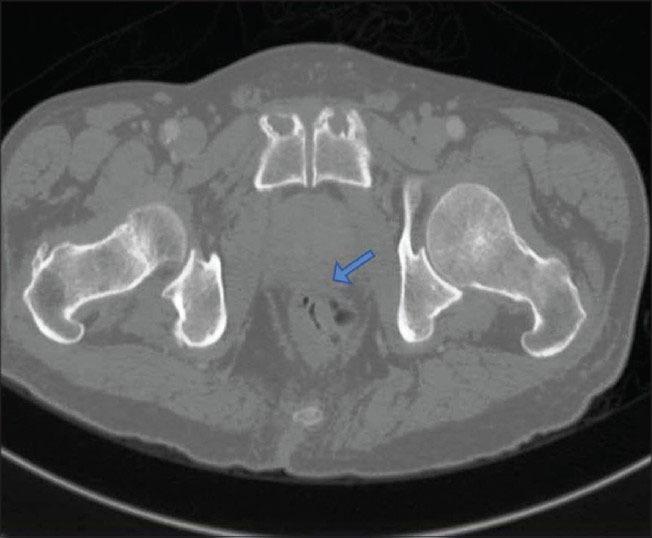

Large B-cell non-Hodgkin lymphoma involving the prostate accounts for 0.09% and 0.1% of non-Hodgkin lymphoma. We report a case of prostatic large B-cell non-Hodgkin lymphoma in a 77-year-old male with symptoms of urinary retention most probably due to benign prostate hyperplasia. He underwent multiple needle core biopsies through transrectal ultrasound of the prostate. Histopathological examination of the core biopsies revealed diffuse infiltration by atypical lymphoid cells in the prostatic stroma, which was strongly positive for leukocyte common antigen and CD20. CD3, CK, PSA, BCL2, k-light chain, Cyclin D1 and synaptophysin were negative. Histopathology and immunohistochemical profile in the case was consistent with the diagnosis of diffuse large B-cell non-Hodgkin lymphoma of the prostate.